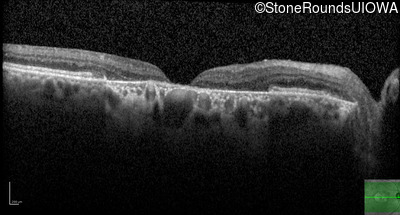

Pattern Dystrophy (IIC)

Age at visit: 47 years

This 47 year man first experienced some decrease in his central vision about 10 years ago.